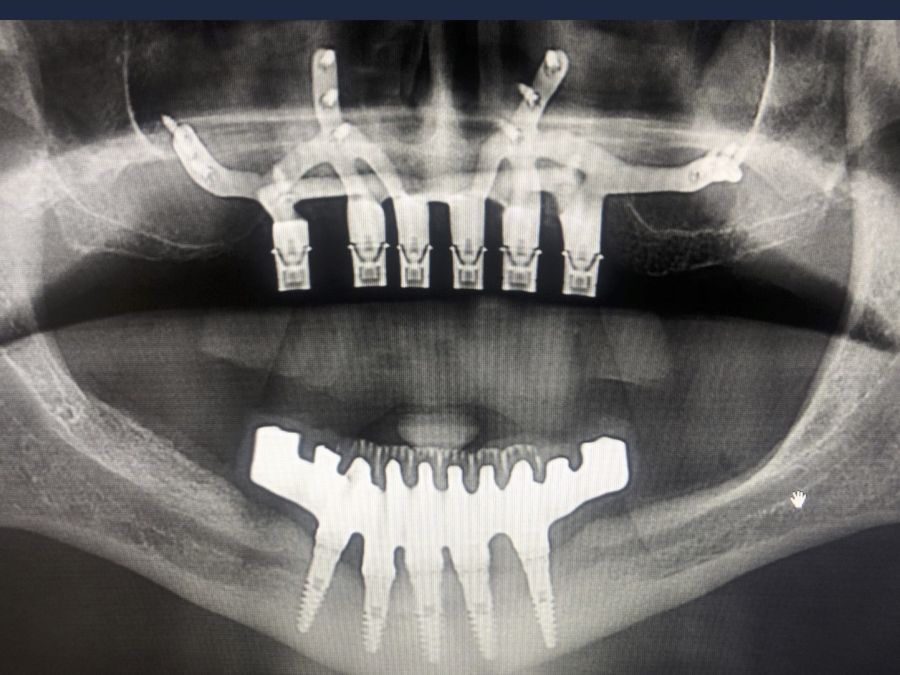

For this purpose, intraoral photographs were made and the complete prosthesis of the patient was used for the different planning tests. First, the double scanning technique was used, adding different radiopaque markers with gutta percha in the prosthesis10 (Figure 3). Then, the scanning was obtained with a conical beam computerized tomography (CBCT), (Planmeca ProMax 3D, Helsinki, Finland), both the prosthesis and the patient with his prosthesis stabilized with a silicone bite registration (Figure 4). In addition, an intraoral scan of the patient’s prosthesis was performed. From this, a personalized structure was designed subperiosteal sintered in Titanium (Ti-6-4) (Custom 3D®) with 6 Multi-Unit® type connections (Branemark, Nobel Biocare) and fixed with osteosynthesis screws in the higher density and volume areas of the malar bone and upper jaw (Figure 5 and 6). At the same time, with the STL digital test of the planning of the mesh, and with the scanning of our complete prosthesis, the laboratory technician made an implantosupported rehabilitation milled in polymethylmethacrylate (PMMA) with Multi-Unit® type titanium interfaces for immediate loading (figures 7 and 8).

The surgical procedure was performed under general anaesthesia and nasotracheal intubation. A supracrestal incision and detachment of a maxillary flap of total thickness was made (Figures 9 and 10). The boundaries of the dissection were both infraorbital ridges, both laterally malar bodies and the anterior half of the hard palate caudally. In addition, a customized cutting guide was used so that the SI was completely in direct contact with the bone (Figure 11) and the mesh was fixed with the different 1.5 mm osteosynthesis screws in the nasal and zygomatic buttresses (KLS Martin, Freiburg, Germany) (Figure 12). The closure was performed with nonresorbable suture. Finally, the PMMA provisional rehabilitation was screwed for the immediate load, with a torque of 20 N on the implants (Figures 13-15).

Two months later, with the soft tissues healed around the connections (Figure 16), a new intraoral scanning was made of the implants and the provisional prosthesis for future restoration. A FRI type passivity test (rigid impression splint) was manufactured with an aluminium structure to assess the correct fit on the implants (Figure 17). For implant-supported rehabilitation, a sintered structure was made in chrome-cobalt with machined bases covered with acrylic resin teeth from Bredent® (Figures 18-21).

The patient has been checked every six months this year, performing X-rays and cleaning the structure, without finding any prosthetic or periodontal complications.